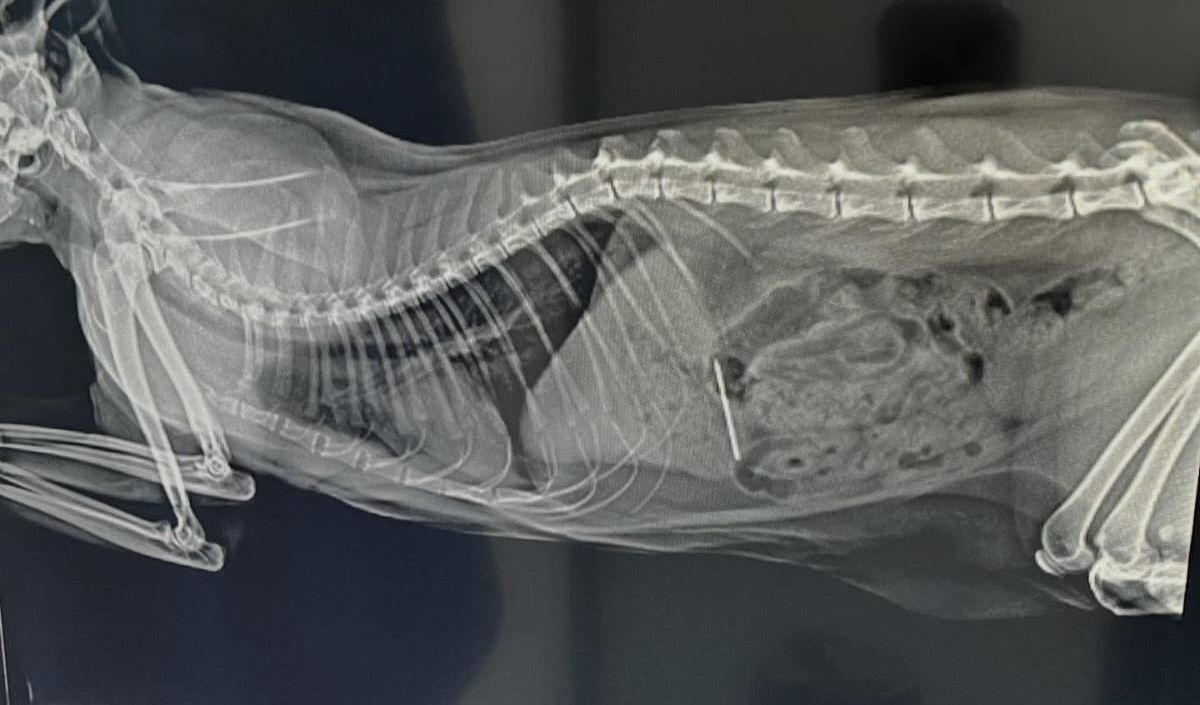

Yozgat’tan Kayseri’ye iştahsızlık ve uykusuzluk şikayetiyle bir veteriner kliniğine muayeneye getirilen kedinin röntgeninde ipe bağlı dikiş iğnesi yuttuğu belirlendi. Pamuk’un durumunun hayati risk taşıması üzerine hemen ameliyata alındı. Yapılan başarılı ameliyatla Pamuk’un midesinden dikiş iğnesi çıkartıldı.

Yozgat’tan Kayseri’ye gece saatlerinde iştahsızlık ve huzursuzluk şikayetiyle bir veteriner kliniğine acil olarak getirilen kedinin yapılan muayene ve röntgeninde, ip ile birlikte dikiş iğnesini yuttuğu tespit edildi. Çekilen röntgen görüntülerinde iğne ve ucundaki ipin mideye kadar indiği belirlendi. Durumun hayati risk taşıması üzerine kedi acil ameliyata alındı.